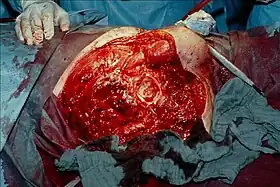

Intraoperative photograph after hemipelvectomy on the right side with view of the acetabulum. This was done for a case of gas gangrene. | |